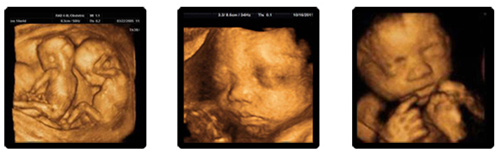

越來(lái)越多的媽媽選擇四維彩超來(lái)做孕期檢查,和普通彩超相比,四維彩超直觀,立體,全方位成像,能夠更好地觀察胎兒的生長(zhǎng)發(fā)育情況,但是也有不少媽媽并不清楚做四維彩超的一些注意事項(xiàng),做四維彩超要空腹嗎?

安琪兒婦產(chǎn)醫(yī)院斥巨資引進(jìn)美國(guó)Voluson E8 TruScan四維彩超,其出色的人體工程學(xué)設(shè)計(jì),每秒鐘可實(shí)時(shí)獲得46幅容積圖像,能直觀、立體的觀察和顯示人體器官的動(dòng)態(tài)和三維結(jié)構(gòu),通過(guò)四維(全方位)立體成像,清晰并動(dòng)態(tài)記錄寶寶在子宮內(nèi)的活動(dòng)和成長(zhǎng)歷程。該技術(shù)獲得美國(guó)FDA認(rèn)證,不存在射線,光波和電磁波等方面的輻射,為您和寶寶提供健康保障,使您輕松愉悅的享受和寶寶的第一次“約會(huì)”。